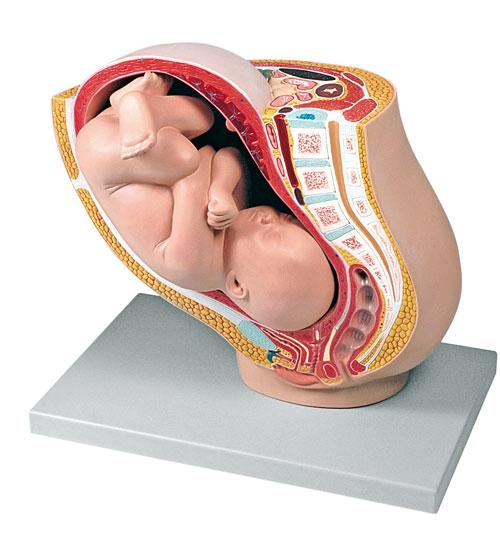

Физиология беременности: строение органов